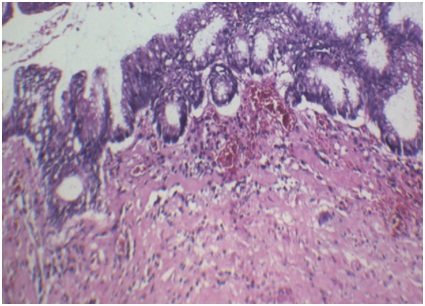

Histopathological analysis of the surgical specimen presentedcecal appendixw ith 5.0x3.0cm. Presence of low grade, well differentiated appendicular mucinous neoplasia with extension in every organ, with tumor free margin and lymph nodes without involvement (Figure 3).

Figure 3: Histopathological analysis of the appendix, H&E stain. Presented dysplastic epithelium, sometimes venous, sometimes tubular, with a presence of mucin in the cytoplasm of the cell.